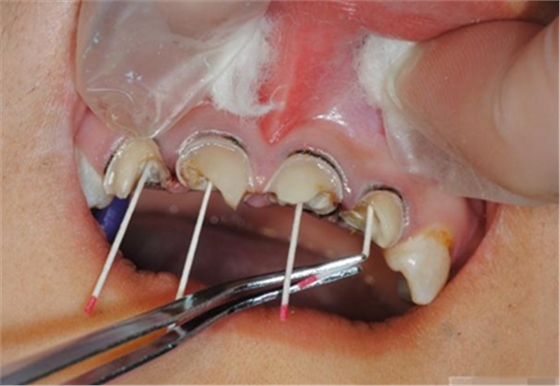

【纖維樁制作】

修整纖維樁長(zhǎng)度

取出纖維樁,按所需長(zhǎng)度裁截纖維樁 在有水條件下 用切割砂片或車針截取纖維樁,切勿使用鉗子,剪刀或鑷子以免破壞樁的結(jié)構(gòu)

涂布硅烷偶聯(lián)劑

涂布粘接劑

將樹(shù)脂粘接劑均勻涂抹在根管、牙體的粘接面以及纖維樁表面,涂抹兩遍

粘接

將調(diào)好的樹(shù)脂水門汀用口內(nèi)注射頭送入根管

將纖維樁表面涂滿調(diào)好的樹(shù)脂水門汀,安放在根管內(nèi)就位,保持壓力10秒